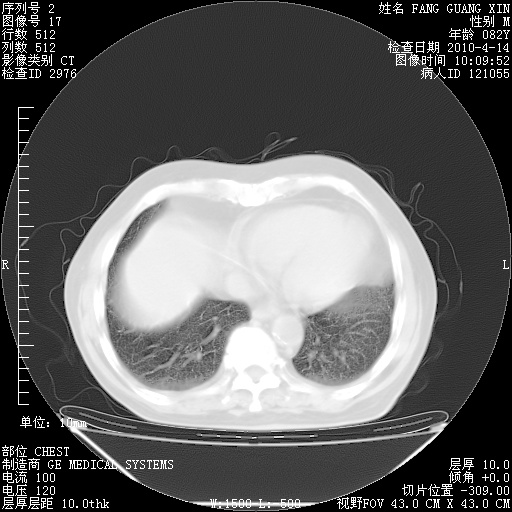

4月14日肺部CT

23.JPG

24.JPG

25.JPG

26.JPG

肺部CT平扫未见异常。